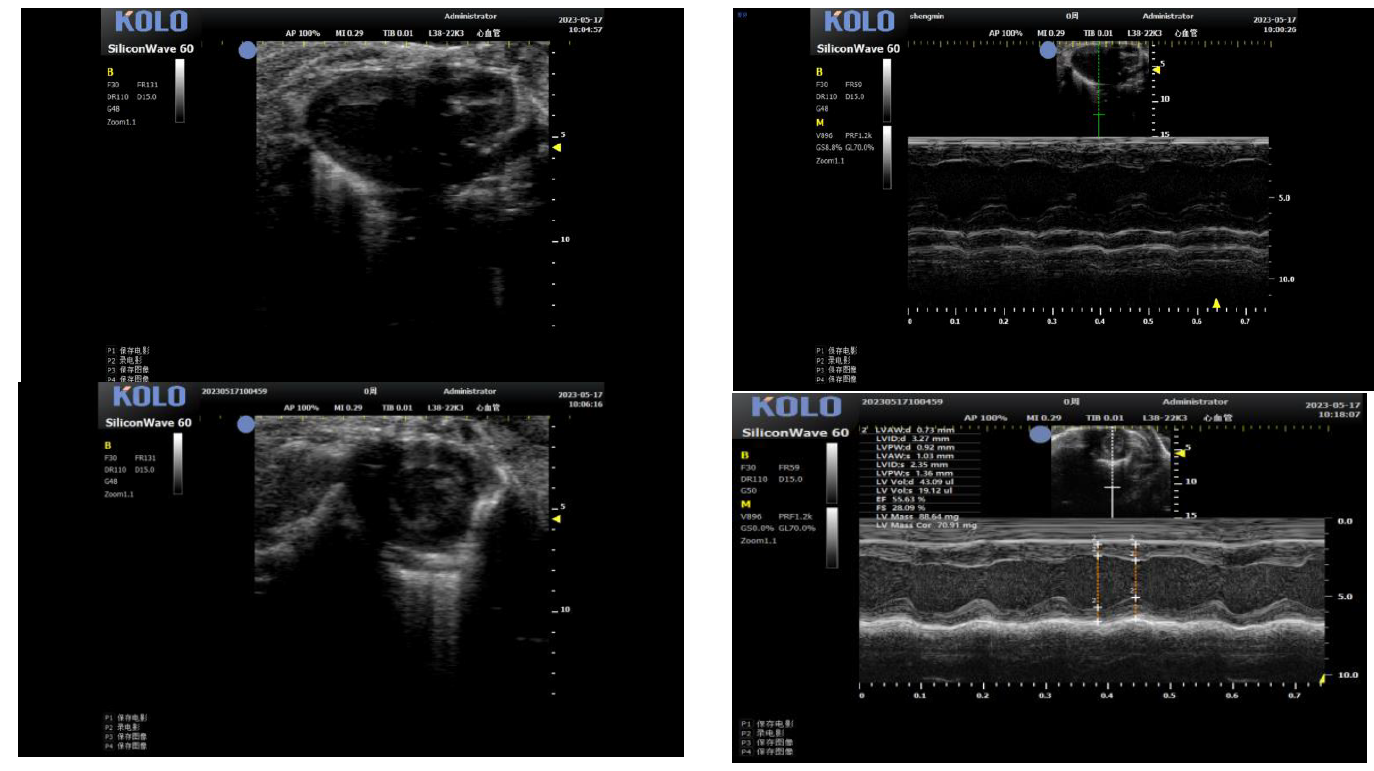

1. 小鼠心脏研究---左心室(长+短轴+M 超)

2. 小鼠心脏研究---四腔心(长轴+血流测速)

3.1 腹主动脉(长+短轴+管壁距离测量+血流流速)